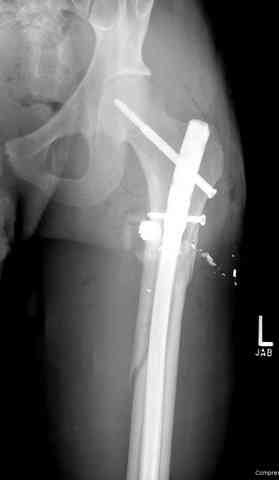

1 Проксимальный перелом бедра, антеградный гвоздь